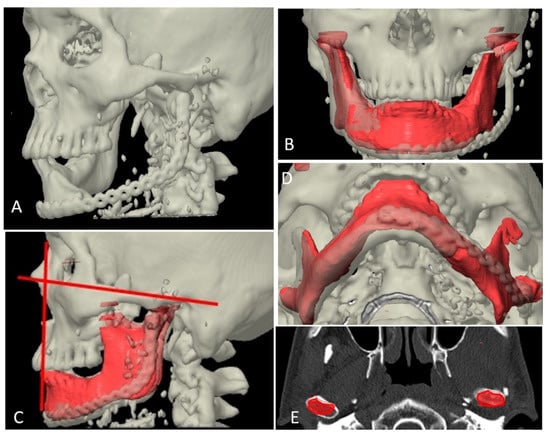

Figure 10.

Superimposition of planned and postoperative image in category III. (A) 3-dimensional view of outcome after reconstruction. (B) Superimposition of virtual plan (red color) and post-operative data. (C) Axial view showing matching of reconstructed fibula to simulated mandible. (D) Sagittal view showing matching of reconstructed fibula to simulated mandible.